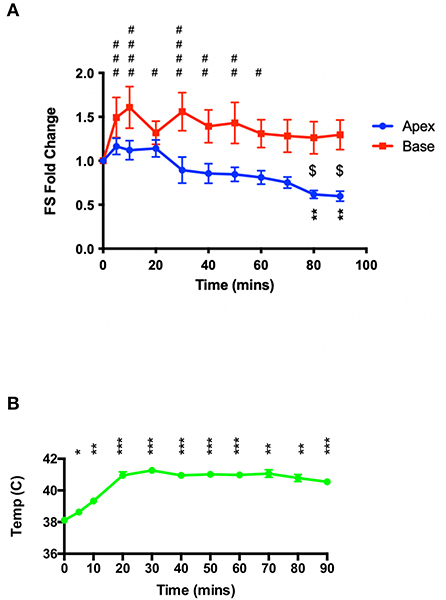

TTS-like contractility can be recapitulated with a 50 mg.kg–1 isoproterenol dose when the hyperthermic response can manifest

As shown in Figure 2, 50 mg.kg−1 isoproterenol, when administered under ketamine-midazolam anesthesia, causes a hyperthermia response that was, in initial studies, attenuated to maintain a euthermic temperature. In a second set of studies, animals were allowed to reach 41°C and maintained at that temperature throughout the 90 min of serial echocardiographic recording post-isoproterenol. This resulted in a negative inotropy in the apex at the 80 and 90 min timepoints compared to baseline, and a significant difference in inotropic change between apex and base at the 80 and 90 min timepoints (Figure 3). Heart rates for these animals can be found in the Supplementary Data.

Figure 3. High-dose isoproterenol (50 mg.kg−1) administration under hyperthermic conditions (~41°C) results in apical-hypocontractility. (A) 50 mg.kg−1 isoprenaline under ketamine-midazolam anesthesia resulted a significant positive inotropic response was seen in the basal myocardial segment for the first 60 min, whereas the apical myocardial segment showed a significant negative inotropic response at 80 and 90 min post-isoprenaline. **P < 0.01 apex vs. baseline; $P < 0.05 apex vs. base; #P < 0.05, ##P < 0.01, ###P < 0.001, ####P < 0.0001 base vs. baseline, two-way repeated measures ANOVA (n = 6). (B) Sustained heating of the animal maintains a significant elevated body temperature post-isoproterenol. *P < 0.05, **P < 0.01, ***P < 0.001 relative to baseline temperature, one-way ANOVA (n = 6 animals).